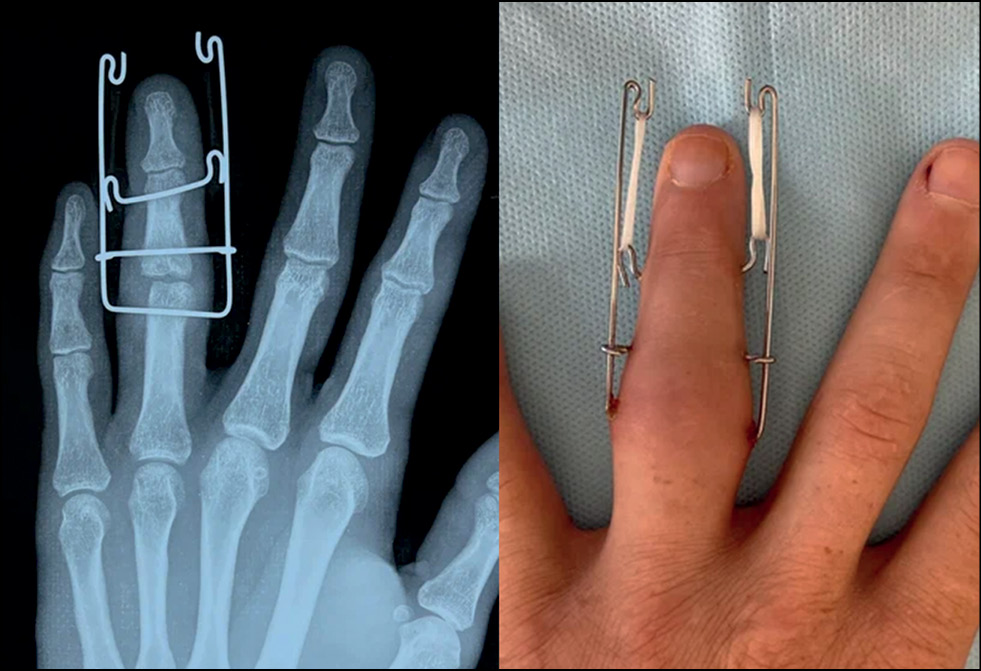

Ортезирование

Ed McElfresh описал технику блокирующего ортеза в 1972 году. Этот метод включает проведение закрытой репозиции, а затем рентгенологической оценки для определения амплитуды движения до появления подвывиха. Затем ПМФС удерживают в дополнительном сгибании на 10–20° от точки, где появляется подвывих. В пределах ортеза (рис. 10) начинается ранняя разработка движений. Допустимая степень разгибания постепенно увеличивается с течением времени, пока ортезирование не будет прекращено. Данный метод эффективен, однако ортез может быть громоздким и требует соответствующего терпения и готовности мириться с определёнными неудобствами. Кроме того, McElfresh и Dobyns рекомендовали это лечение пациентам с переломами 30% или менее суставной поверхности и некоторым лицам с переломами 30–50%, хотя они заявили, что у таких пациентов необходимо рассмотреть возможность хирургического вмешательства [17].

Рис. 10. Варианты ортезирования [7, 12, 22].

Fig. 10. Orthotization options [7, 12, 22].